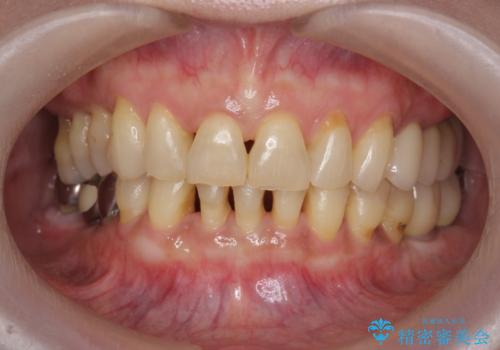

総合歯科治療 → 歯周病治療&矯正歯科治療

- [ 歯周病・矯正・セラミック治療 ] 1つの医院で行う包括的歯科治療- 担当医 大元洋佑 ![[ 歯周病・矯正・セラミック治療 ] 1つの医院で行う包括的歯科治療の症例 治療前](https://seimitsushinbi.jp/wp/wp-content/uploads/2023/10/IMG_6364-500x350.jpg?v=1697786419) ![[ 歯周病・矯正・セラミック治療 ] 1つの医院で行う包括的歯科治療の症例 治療後](https://seimitsushinbi.jp/wp/wp-content/uploads/2023/10/90d18252b8dbe1975afad5c7598b2fb5-500x350.jpg?v=1697785801)